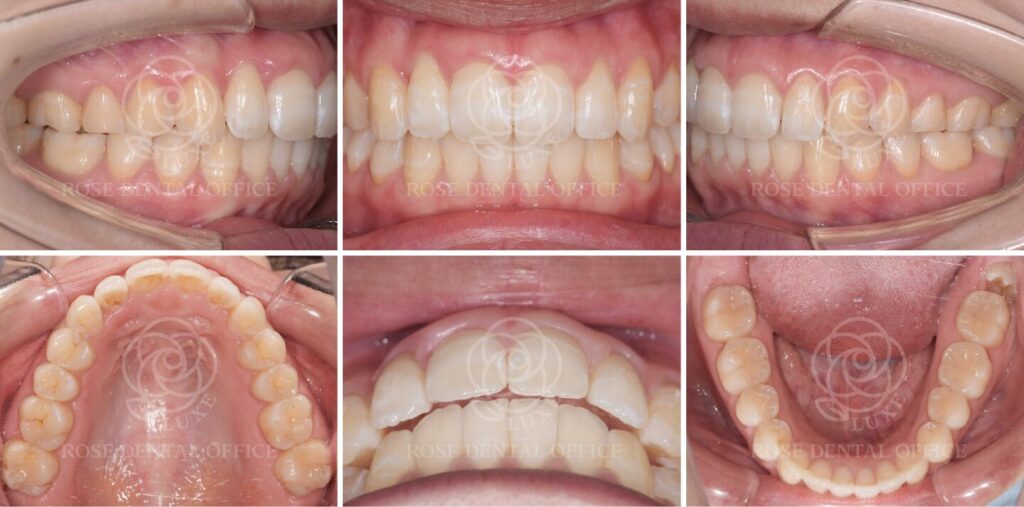

上の前歯の捻転と突出感をインビザライン矯正治療で改善 20代女性

インビザライン・コンプリヘンシブ(マウスピース矯正・全体矯正)

Before

after